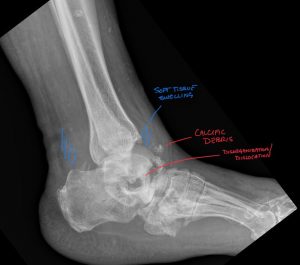

Fig. 4 Annotated xray showing distal tibial fracture with Kager’s fat pad effusion and degenerative changes, including osteophyte and enthesophyte formation